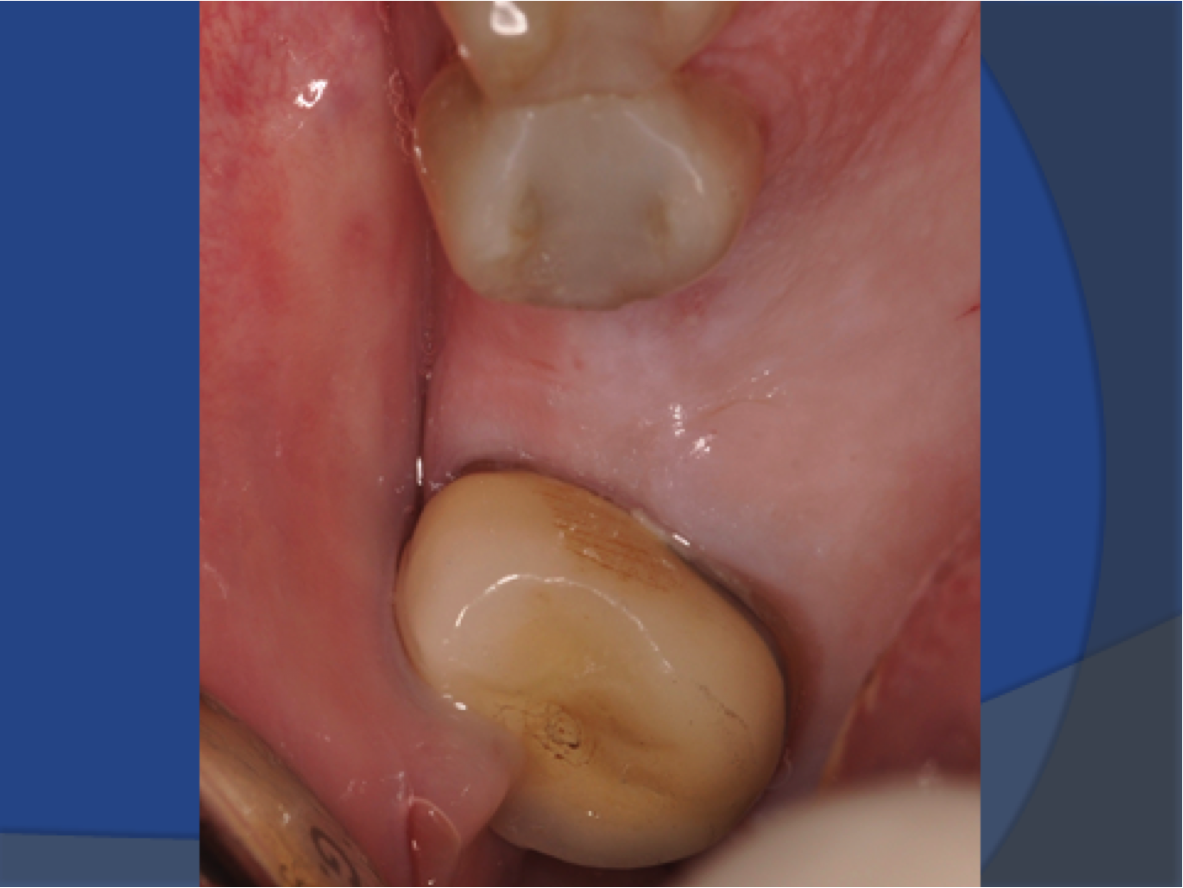

Fig 12. Sufficient attached mucosa was evident after 6 months of healing.

Figure 12

In this case, the patient’s right maxillary first molar had been extracted, and the site was grafted. The periapical radiograph taken after 6 months of healing indicated the presence of dense bone (Figure 11). There was also ample attached mucosa (Figure 12). Impressions were taken, a diagnostic cast was made, and a wax-up of the restoration was placed in the model (Figure 13). To make the radiographic guide for this case, a silicone putty index was created over the diagnostic wax-up, as described earlier. A panoramic radiograph and a CBCT scan (Figure 14) were taken with the radiographic guide in place; the guide post in the index can clearly be seen.